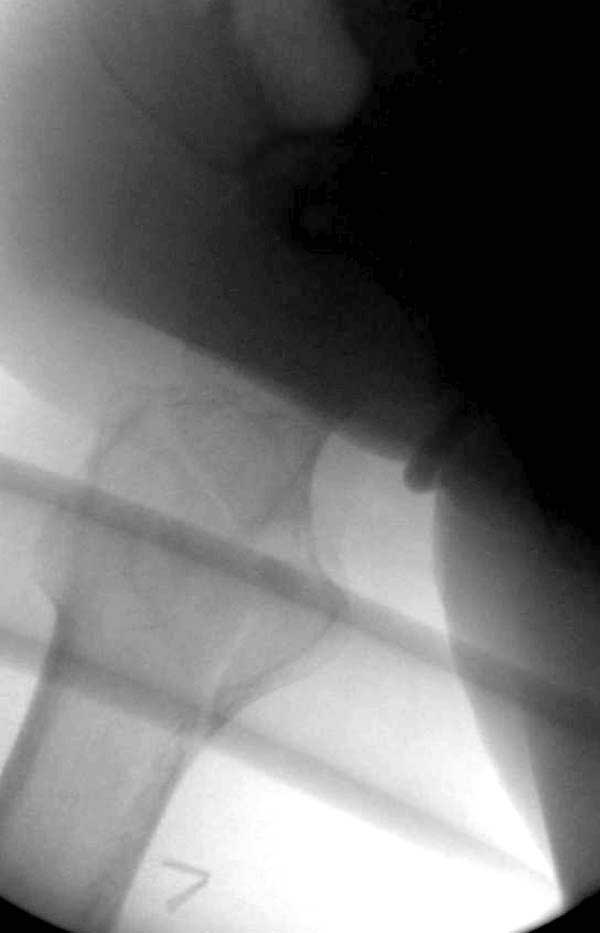

Первые снимки показывают технические погрешности установки DHS. Не была достигнута репозиция, конечность в флексии и шейка в ротации. Сегодня все меньше обращают внимание на параметры для оценки репозиции (S контуры Lowell в обеих проекциях и Garden Alignment Index, в норме 155 и 180 градусов), хотя такие простые тесты помогли бы дорепонировать смещение. Винт находится сзади в головке, что при нагрузке поменяет вектор и вместо компрессии в линии перелома срежет головку-Cut Out!